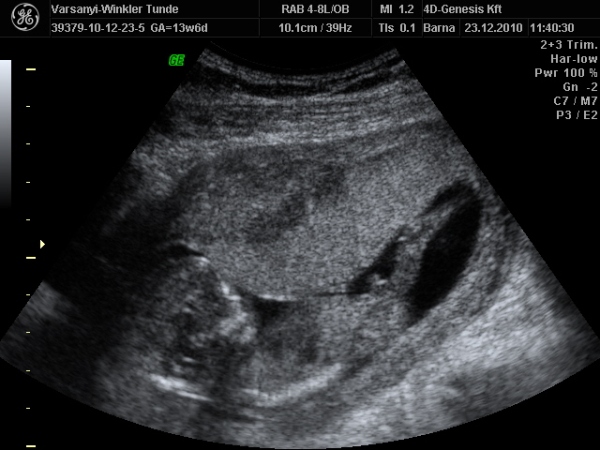

Bár tegnap a dokor bácsi azt mondta, hogy azért lassan vissza kellene vennem a lendületből, mert nem lesz jó vége. Manócska jól van, de tegnap nem tudtuk megnézni. Hasi uh-val próbálkozott, de pont úgy fordult, hogy csak a nagy kobakját láttuk

Gondolta, ha arra van a feje, akkor lentről lehet látni valamit a neméből.

Be is terpesztett rendesen, mint egy kis utcalány

Természetesen lánynak is látszott, bár azt mondta, hogy még ne éljük bele magunkat. A férjem le is tört egy kicsit, de nem vallotta volna be.Holnap reggel megyek AFP-re.